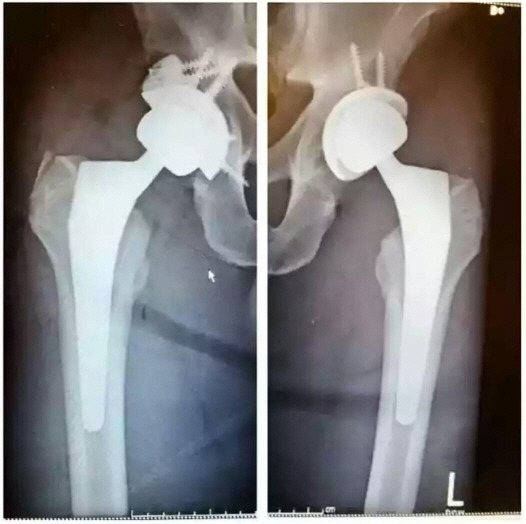

로니 콜먼은 보디빌딩 은퇴 후에 고관절 무혈성괴사라는 병이 생겨 양쪽 고관절에 핀을 8개나 박는 수술을 했습니다.

고관절에 핀을 박은 x-ray 모습